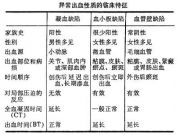

| 2021年7月26日 (一) 20:03 | 异常出血性质的临床特征.jpg (文件) |  |

28 KB | Uploaded with SimpleBatchUpload | 3 |